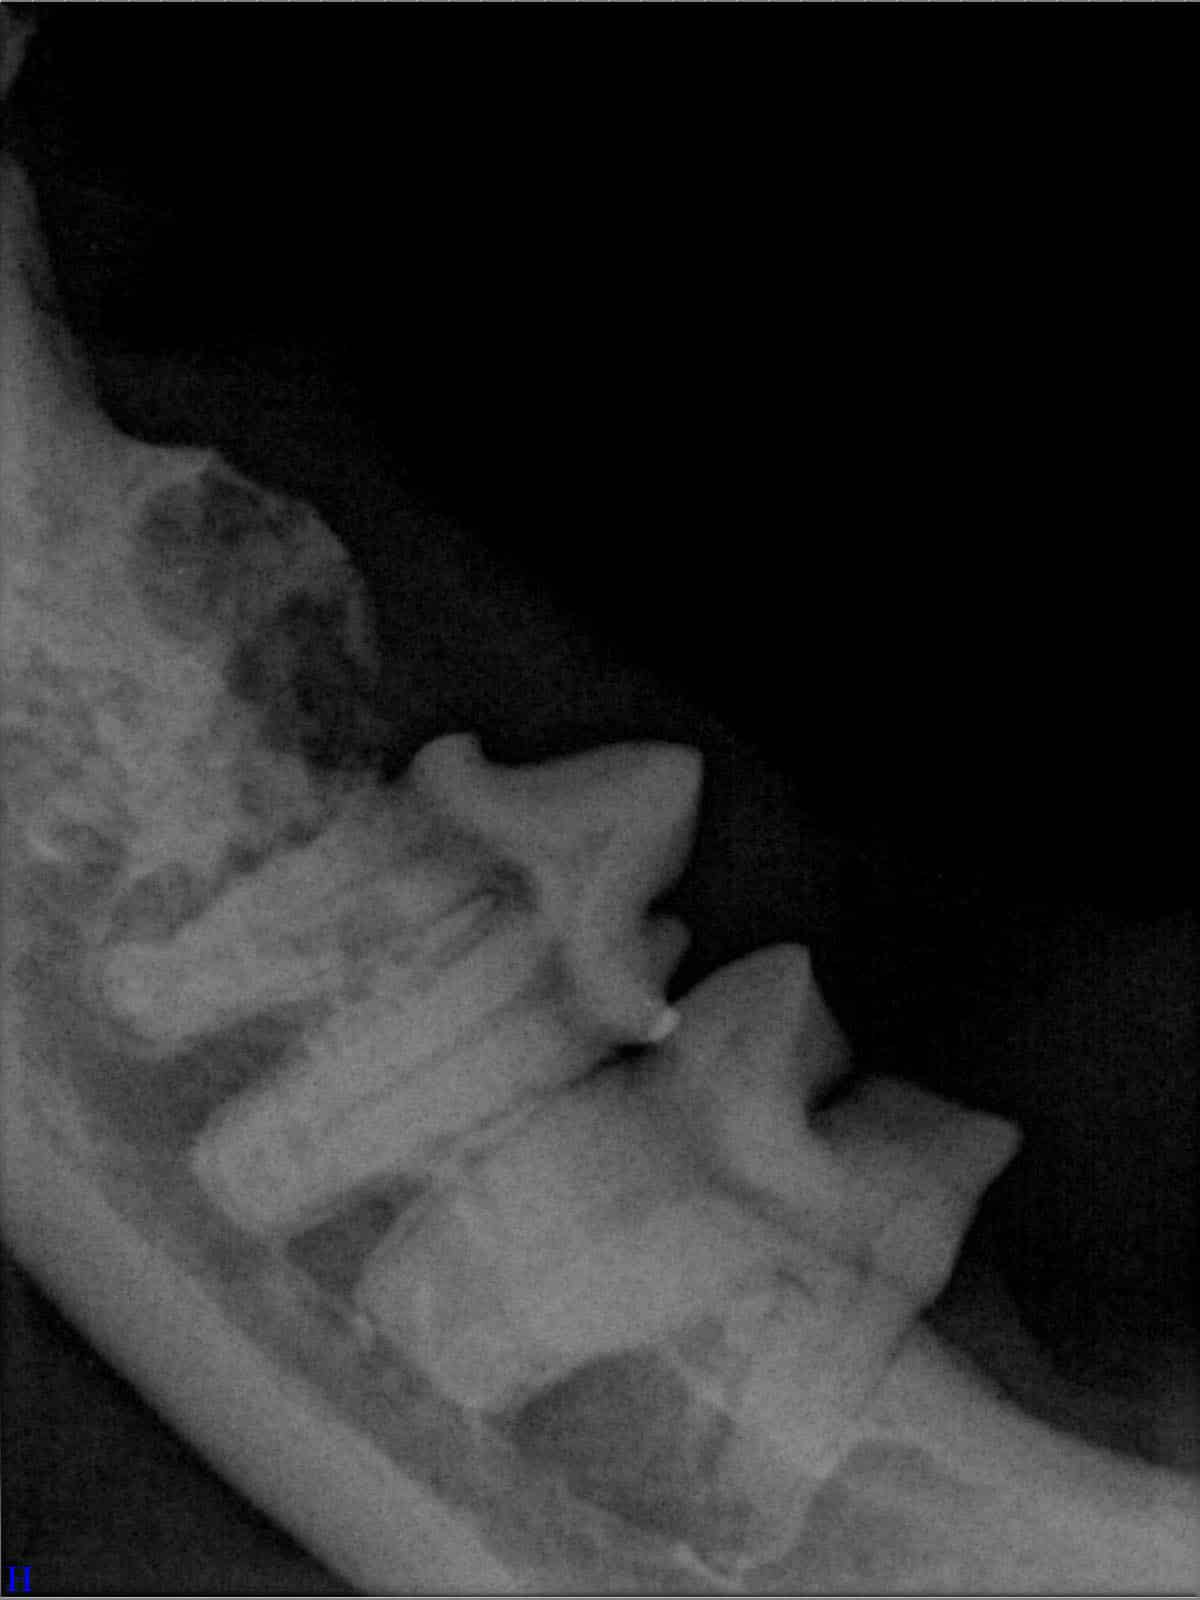

Ein entscheidender Baustein der FORL-Diagnostik ist das dentale Röntgen. Viele Läsionen sind von außen nicht sichtbar und lassen sich ausschließlich mithilfe moderner Röntgentechnik erkennen. In der Hamburger Praxis kommt digitales Dentalröntgen zum Einsatz, das detailreiche Aufnahmen bei geringer Strahlenbelastung ermöglicht. So kann FORL bereits in frühen Stadien diagnostiziert werden.

Das sehen Sie von außen – so sieht es auf den Röntgenbildern aus.

FORL Katze Röntgenbild

Röntgenbilder